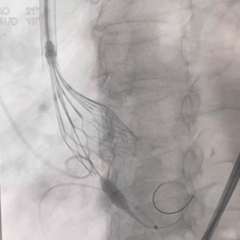

再次回收,第三次释放

全展开造影,大弯侧0位

左侧位造影,小弯侧深度可

脱钩后造影,瓣膜位置可